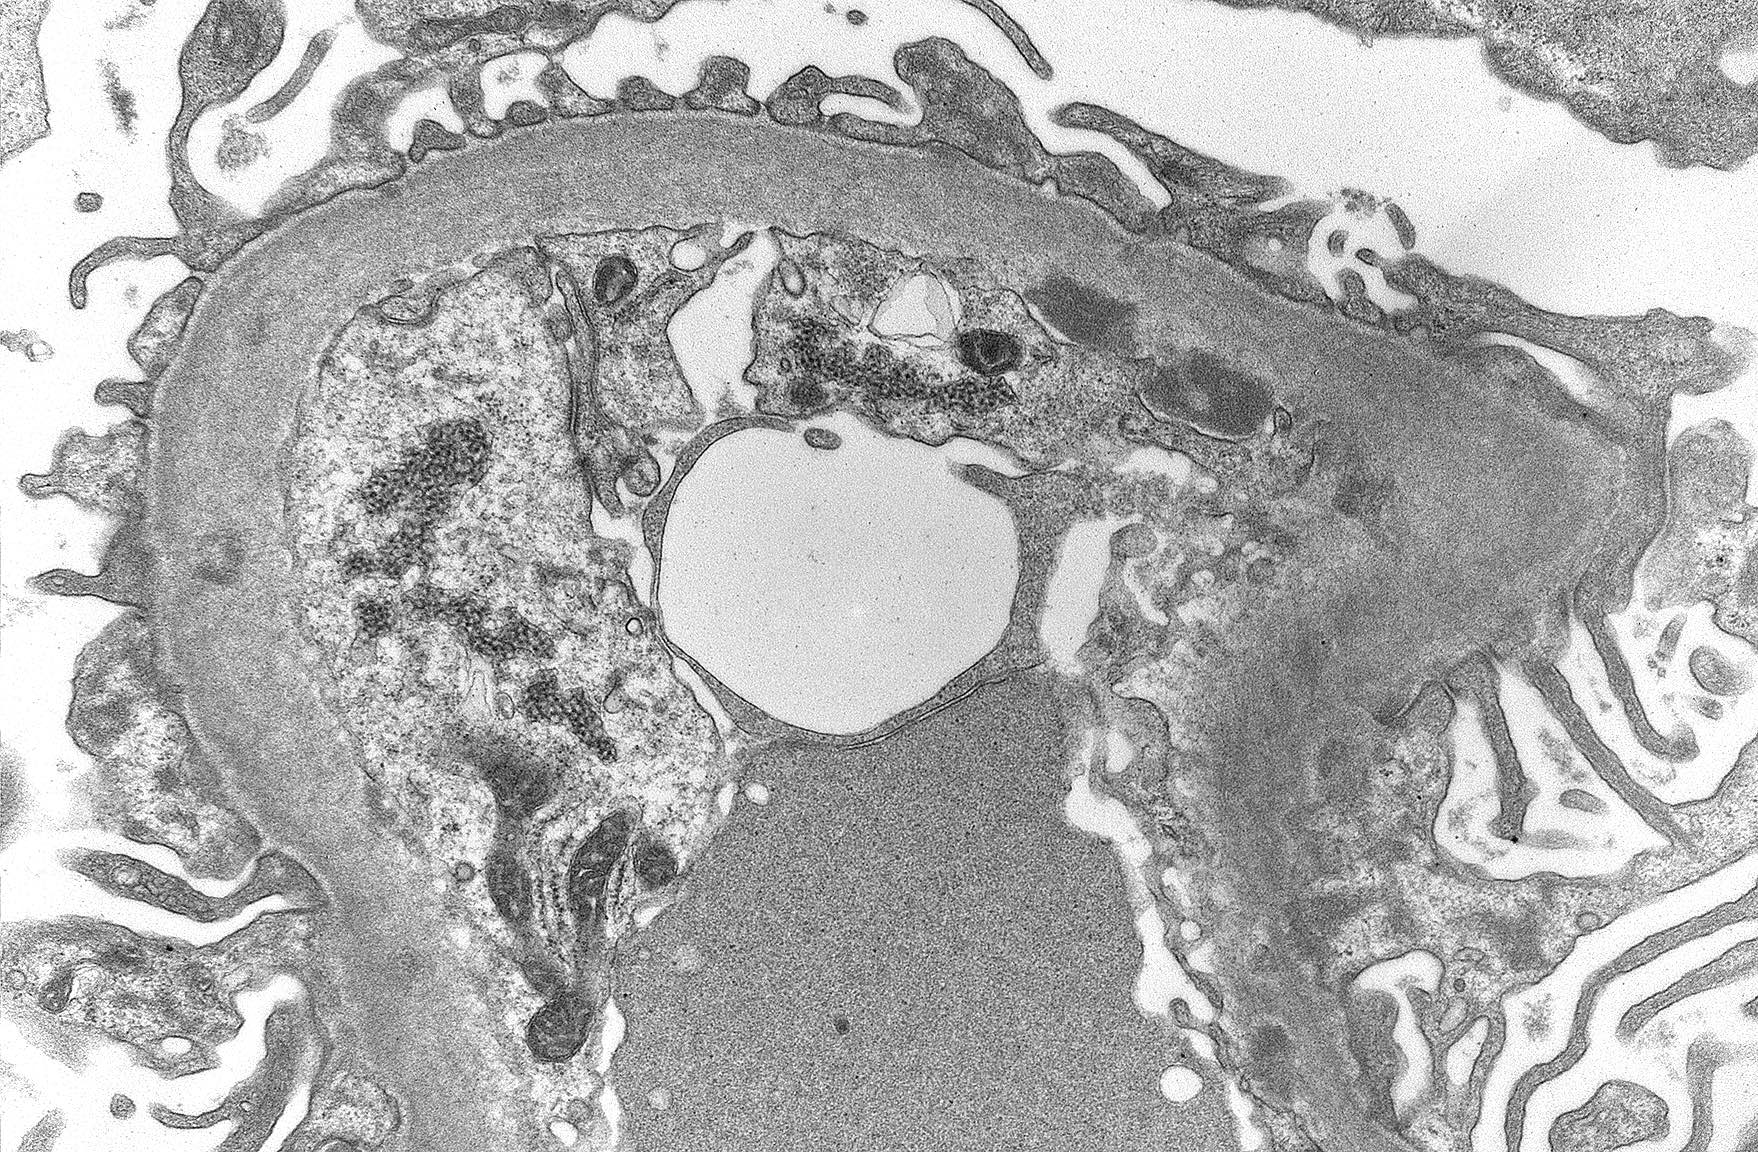

Electron microscopy description

- Finalizes the classification of lupus nephritis for a given case

- Granular electron dense deposits (smaller in LN classes I - II and larger in classes III - IV) are seen in subepithelial, intramembranous, subendothelial and mesangial locations; locations are important in determining the LN class

- Subepithelial immune deposits show adjacent neomembrane formation

- Immune deposit substructure may be present

- Tubuloreticular inclusions: reticular aggregates of branching membranous tubule within the cisternae of endoplasmic reticulum found within the endothelial cells are useful in establishing the diagnosis of lupus erythematosus; are also found in other conditions with elevated levels of interferon (Pathology 2019;51:727)

Electron microscopy images

- Electron microscopy: Glomerular basement membranes are of normal thickness. Numerous subendothelial electron dense (immune complex) deposits are seen. There is mild segmental podocyte foot process effacement. Capillary lumens are patent. The mesangium shows a moderately expanded mesangial matrix and contains large electron dense deposits.

Biopsy is done on a patient with a history of systemic lupus erythematosus and nephrotic syndrome. Electron microscopy reveals the findings shown above. Which complication is the patient predisposed to?